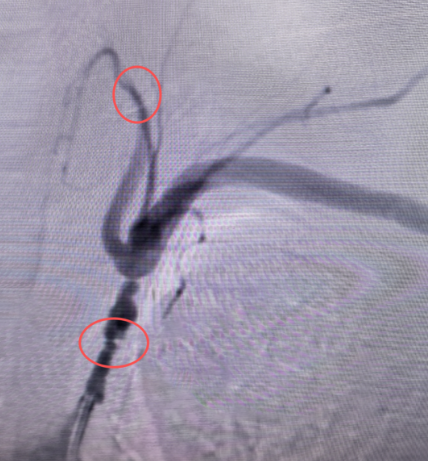

反复头晕、行走不稳就诊,日常活动严重受限,甚至无法独立完成行走等基本动作,严重影响生活质量。入院后,姜福成主任团队立即为患者完善了全脑血管造影等详细检查,结果显示:患者左侧锁骨下动脉存在长节段重度狭窄,同时合并椎动脉盗血,这正是导致患者头晕、行走障碍的“元凶”。

面对患者的迫切需求,姜福成主任团队反复研判造影影像,精准评估血管病变范围、狭窄程度及周围解剖结构,制定了个体化的介入治疗方案。手术中,团队凭借丰富的临床经验和娴熟的操作技巧,精准穿刺、顺利通过狭窄段,成功植入支架,一次性解除了血管狭窄。术后复查造影显示:患者左侧锁骨下动脉狭窄完全解除,血流通畅,原本因盗血而显影不佳的椎动脉全程显影良好,脑部供血恢复正常。